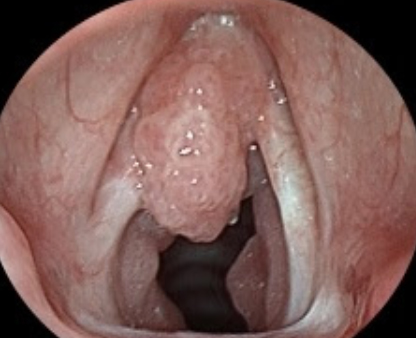

Жалобы, возникающие в зависимости от одностороннего или двустороннего статуса, определяют план лечения (см. Лечение паралича голосовых связок). Образование паутины (паутины) в голосовой связке, которое обычно является врожденным в детстве, но также может появиться в результате некоторых хирургических вмешательств на голосовой связке, в основном затрагивает переднюю 1/3 голосовых связок.Лечение состоит из операции (лазер или холодный нож. Доброкачественные опухоли, также называемые папилломатозом или ювенильным папилломатозом гортани, являются наиболее частыми опухолевыми поражениями в детском возрасте и вызывают большее беспокойство, чем у взрослых. Основная проблема у этих детей – охриплость и затрудненное дыхание, которые развиваеться по мере увеличения массы и сужения дыхательных путей. Вирус папилломы человека (ВПЧ) эффективен при этом заболевании, и папилломатоз гортани чаще всего выявляется при ВПЧ 6 и 11 типов. При осмотре можно увидеть образования, похожие на цветную капусту, на голосовых связках и могут распространятся на окружающие дыхательные пути. В качестве меры предосторожности рекомендуется вакцинация от опасных типов ВПЧ в детстве. При хирургическом лечении ткань удаляется под общим наркозом под микроскопом и с помощью ЛАЗЕРА. Эти опухоли подвержены рецидивам и могут потребовать нескольких хирургических вмешательств.